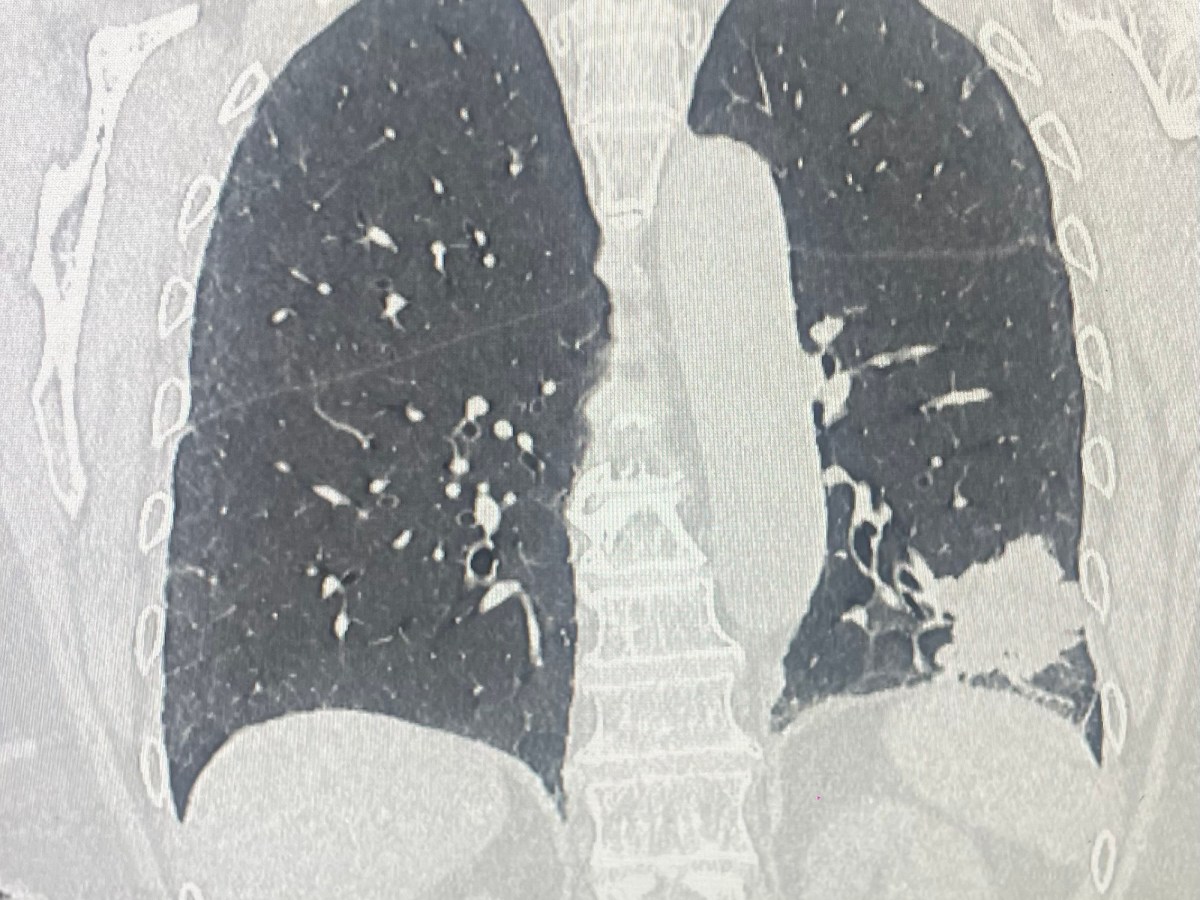

Lobectomia robotica fissure last technique

L’età anagrafica non corrisponde all’età biologica e “di per sé” non è una controindicazione ad interventi di chirurgia toracica maggiore quali la lobectomia per il trattamento del cancro del polmone. La chirurgia mini-invasiva ed, in particolare la tecnica robotica, è particolarmente indicata nel trattamento del cancro polmone nei pazienti ultraottantenni. Il minore trauma chirurgico, la…